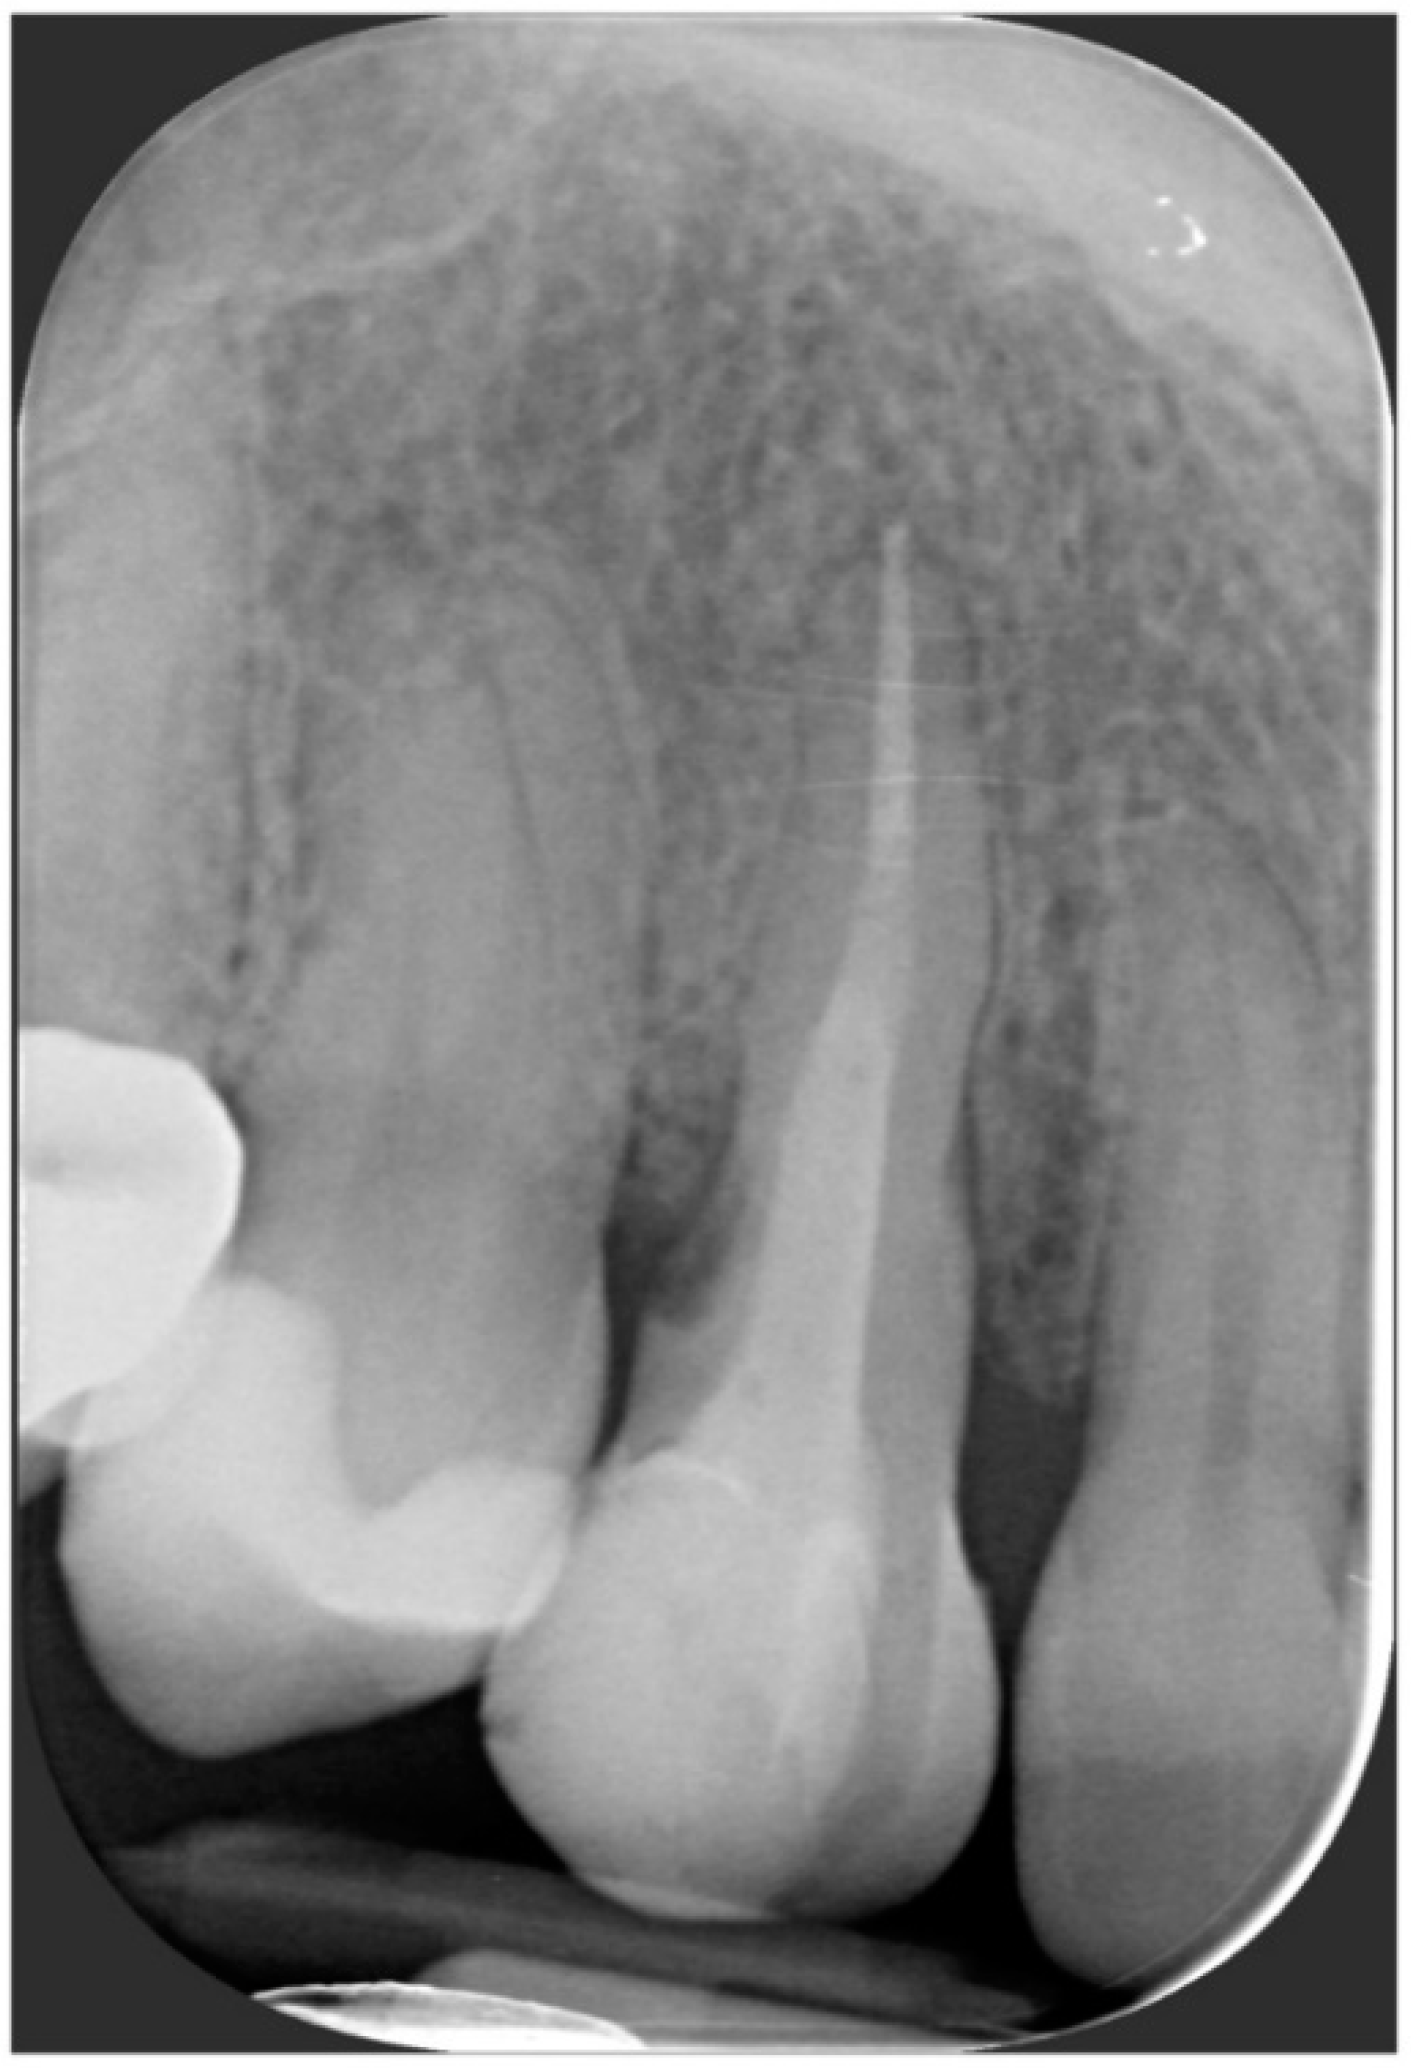

After the complete closure of the papillae, a final sling suture suspended around the cingulum of the implant-supported crown (6/0 PGA thread; 11 mm needle) was performed to obtain a tight adaptation of the flap’s keratinized tissue into the convex, smooth surface of the provisional, a prerequisite for the stability of the surgical wound and for minimizing the risk of flap shrinkage. The absence of blood seeping from the margins is a sign of surgical wound stability, and this can minimize the contraction of the coronally advanced flap. At the end of surgery, an X-ray scan was performed (Figure 12).

One year after final restoration placement, the clinical outcome remained stable and fully satisfied the patient’s esthetic demands (Figure 15a–c). The soft tissues were morphologically and dimensionally stable without any signs of inflammation, and the marginal bone loss evaluated with periodical X-ray scans was minimal (Figure 16).

Figure 12. Radiographic evaluation following implant placement.

Figure 16. Marginal bone loss evaluated with periodical X-ray scans was minimal.